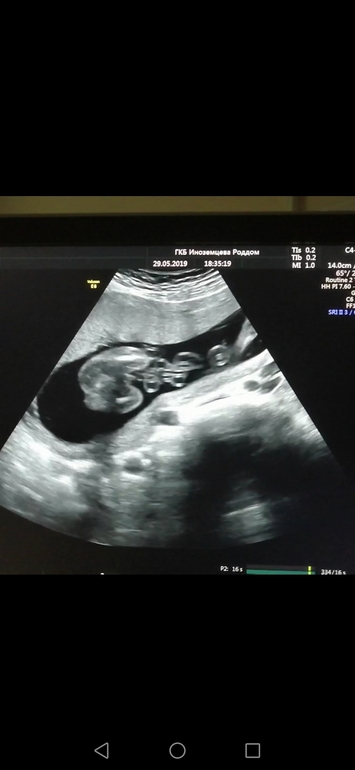

Пол малышаТогда был 2 скрининг (полных 18 недель) в мае 2019, и именно на нём мы узнали, что ждём мальчика. Это нам сказали сразу же, как приложили датчик к животу. Мы даже не спрашивали))) Помню эмоции мои и мужа. Мы так хотели! Никак не могла уложить эту мысль в голове, что ношу мальчика, и бегала довольно часто на УЗИ для подтверждения. Мне ни разу не ошиблись. Разрешили в тот раз, на скрининге, сделать видео. Вот стоп-кадр. Сейчас думаю: и чего я сомневалась или не верила? 🤣 Ну, явно же! ЧуднЫе мы, когда беременные 😜

Если что - фото снизу, с попы.